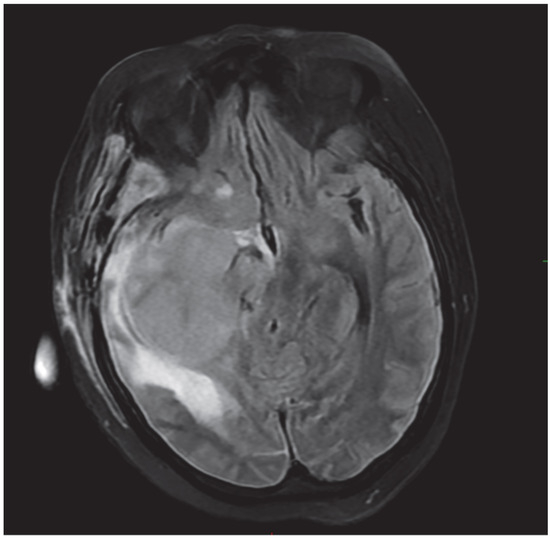

Unusual Dual Brain Tumor Morphologies in an MEN1 Patient: A Case Report of Diagnostic Challenges and Methylation Insights

Multiple Endocrine Neoplasia Type 1 (MEN1) is an autosomal dominant disorder commonly associated with tumor development in the parathyroid glands, pancreas, and pituitary gland. While pituitary adenomas are frequently observed in MEN1 patients, the presence of additional tumors within the pituitary gland is unusual. Moreover, the co-occurrence of a pituitary adenoma with an atypical teratoid/rhabdoid tumor (ATRT) has not been previously documented. ATRT is a rare, aggressive neoplasm predominantly affecting young children and is typically associated with inactivating mutations in the SMARCB1 or SMARCA4 tumor suppressor genes. These mutations result in uncontrolled cellular proliferation, which underlies the malignancy’s rapid progression. In adults, ATRT is exceedingly rare, making this case particularly noteworthy for its uniqueness in both tumor type and patient demographics. ATRTs are now classified into three molecular subgroups—MYC, SHH, and TYR—each with distinct epigenetic and clinical features, further refining diagnostic and prognostic assessments. In this case report, we describe a case of a female patient with MEN1 who experienced several recurrences of pituitary adenoma, ultimately necessitating surgical resection. Detailed pathological evaluation of the resected tissue revealed two distinct neoplasms within the pituitary gland: one typical of a pituitary adenoma, and the other confirmed as ATRT. The diagnosis of ATRT was established through extensive workup including immunohistochemical analysis, next-generation sequencing and methylation profiling, which served as essential tools in distinguishing ATRT from other potential differential diagnoses. This case illustrates the complex diagnostic journey and challenges encountered in identifying ATRT in the context of MEN1, underscoring the importance of using advanced molecular and immunohistochemical techniques in atypical presentations. Furthermore, it expands the understanding of potential tumor associations within MEN1, providing insight for pathologists and clinicians into the rare possibility of concurrent tumors in addition to pituitary adenoma in MEN1 patients. Raising awareness of such co-occurrences could prompt earlier diagnostic considerations by refining the differential diagnosis in patients with MEN1 presenting with unusual tumor types. Full article

Figure 1